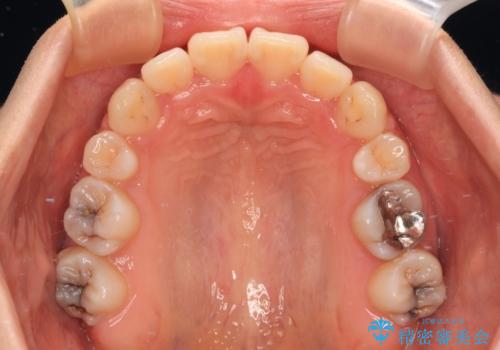

上下前歯がくちばしのように突出していましたが、抜歯矯正により口元が引っ込み、唇が閉じやすくなり、鼻の下の膨れた感じも解消されました。